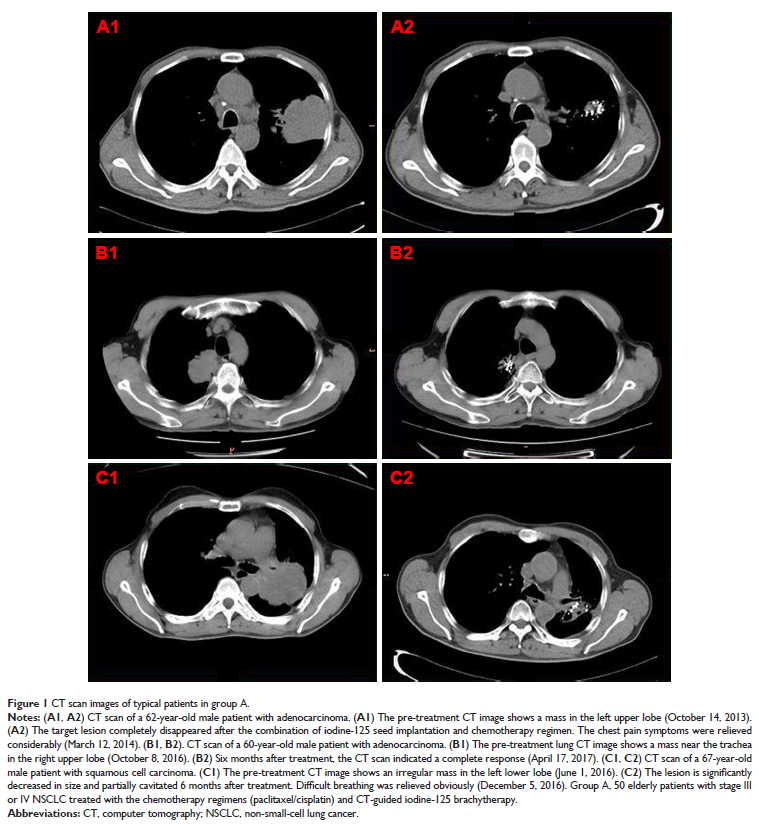

碘-125 粒子近距离放疗联合化疗治疗老年晚期非小细胞肺癌的有效性及安全性研究